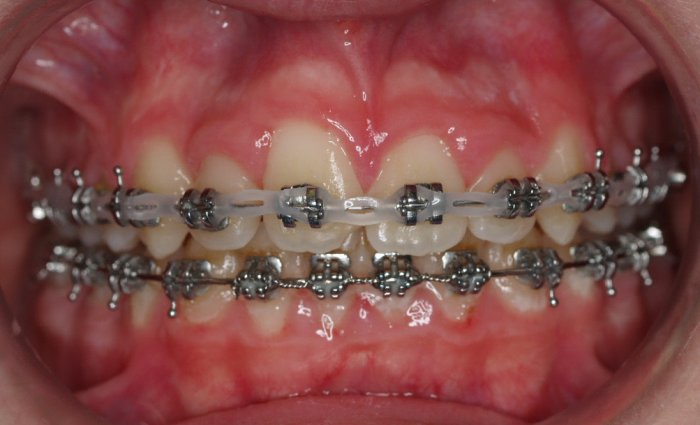

- Realizar un tratamiento ortodóncico para mover los dientes y cerrar el diastema.

Si su frenillo labial es demasiado grande, puede que le remitan a un especialista para someterse a un procedimiento quirúrgico llamado frenectomía. Este procedimiento consiste en cortar el frenillo y volverlo a colocar para permitir que tenga más flexibilidad. Cuando la frenectomía se realiza en un niño, el espacio puede llegar a cerrarse por sí solo. Si se trata de un adolescente o un adulto, puede que sea necesario cerrarlo con ortodoncia. Es esencial acudir al dentista para saber cuál de estas opciones es la adecuada en su caso.